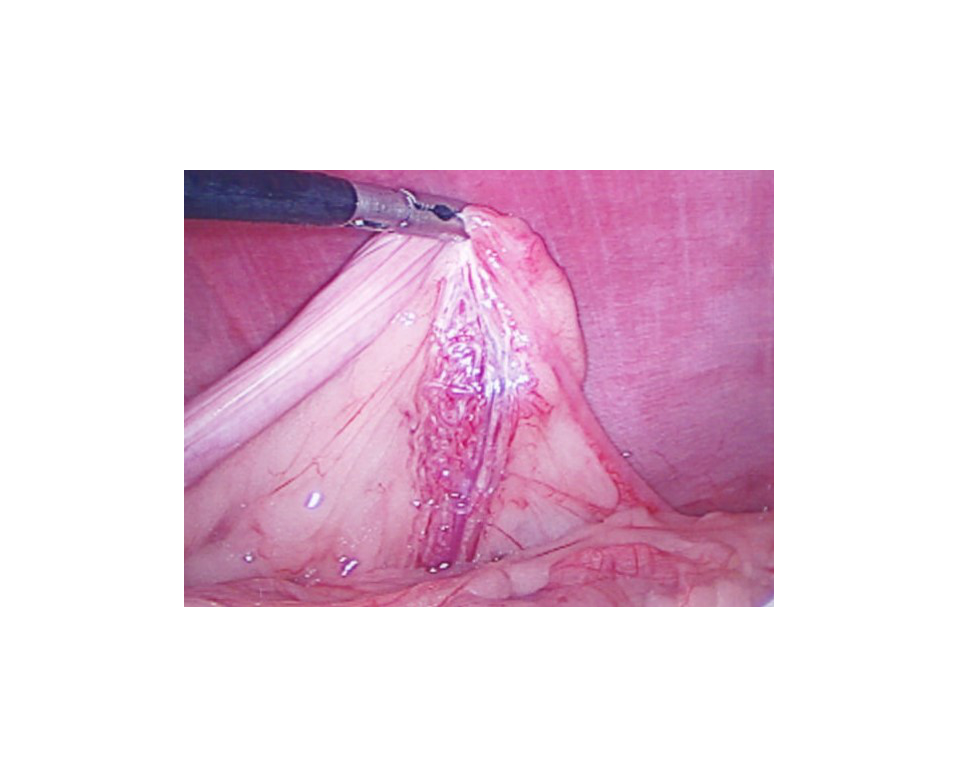

The ovary is identified and temporarily fixed to the abdominal wall: